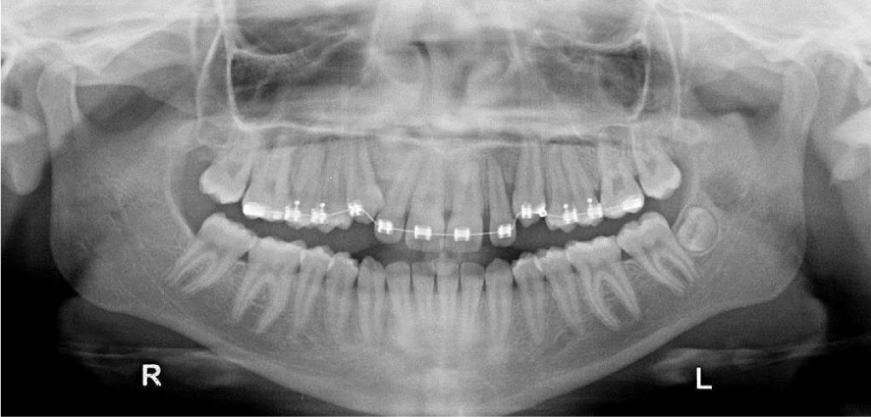

During the treatment two end oral radiographs were made on each side to ensure that the movement of canine was not damaging the roots of the neighboring teeth. When the crowns were erupted a metallic canine bracket was bonded, and the remaining movements were made with sectional, later repositioning the bracket twice. A Flexiloy tm 0.021 X 0.025 was the finishing arch and an Essix retainer was used for retention. The active treatment lasted 2 years long. Both the canines at the end of treatment had good periodontal conditions (Figure 2d, 3a-c).

The results of this case treatment showed the bilateral impacted maxillary canines were corrected. Acceptable occlusion achieved and the over jet and overbite come to normal [31]. The molar and canine relation were Class I on the both sides. Lateral cephalometric showed overall facial balance was improved. The lip becomes less tension on closure. No signs or symptoms of temporomandibular dysfunction after treatment [32].